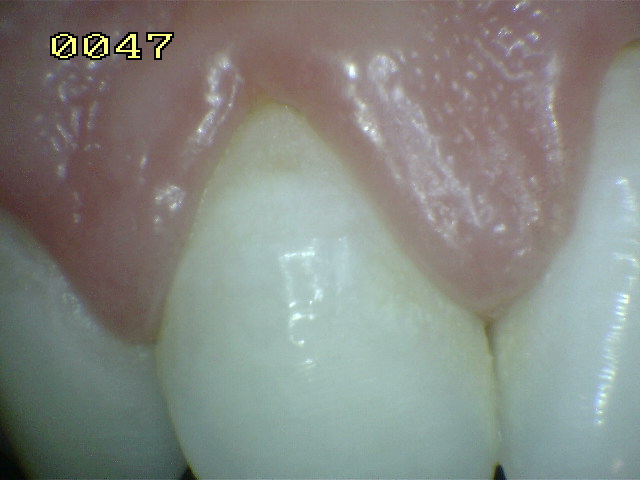

Encía levemente inflamada con un

componente fibroso. Observe el borde gingival con aspecto

liso, turgente y brillante de color rojo |